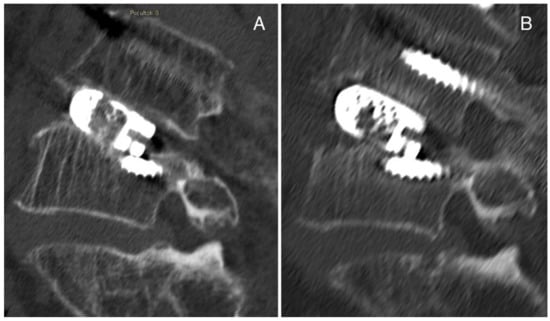

3.8. Representative Cases of Complications from Our Institution